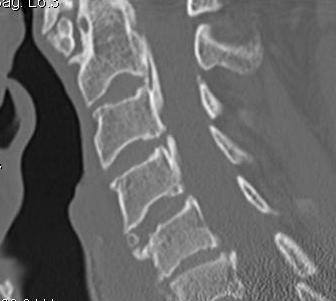

CT

Helps distinguish disc from osteophytes

- soft v hard disc

- diagnose OPLL

OPLL on CT

MRI and CT in same patient with OPLL